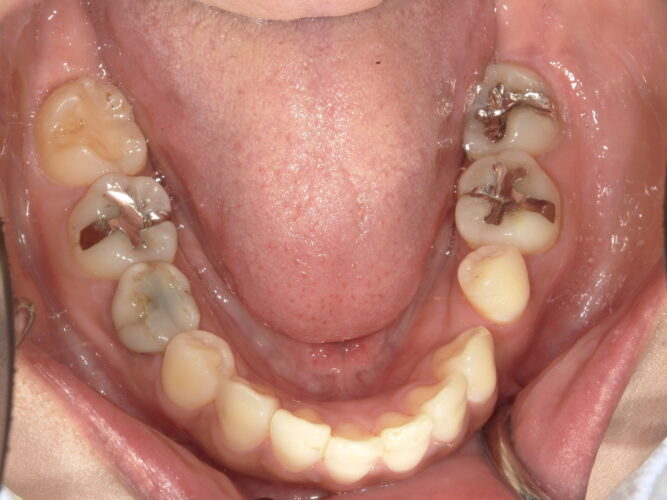

矯正後

約1年程矯正治療を行いインプラント埋入スペースを確保しました。